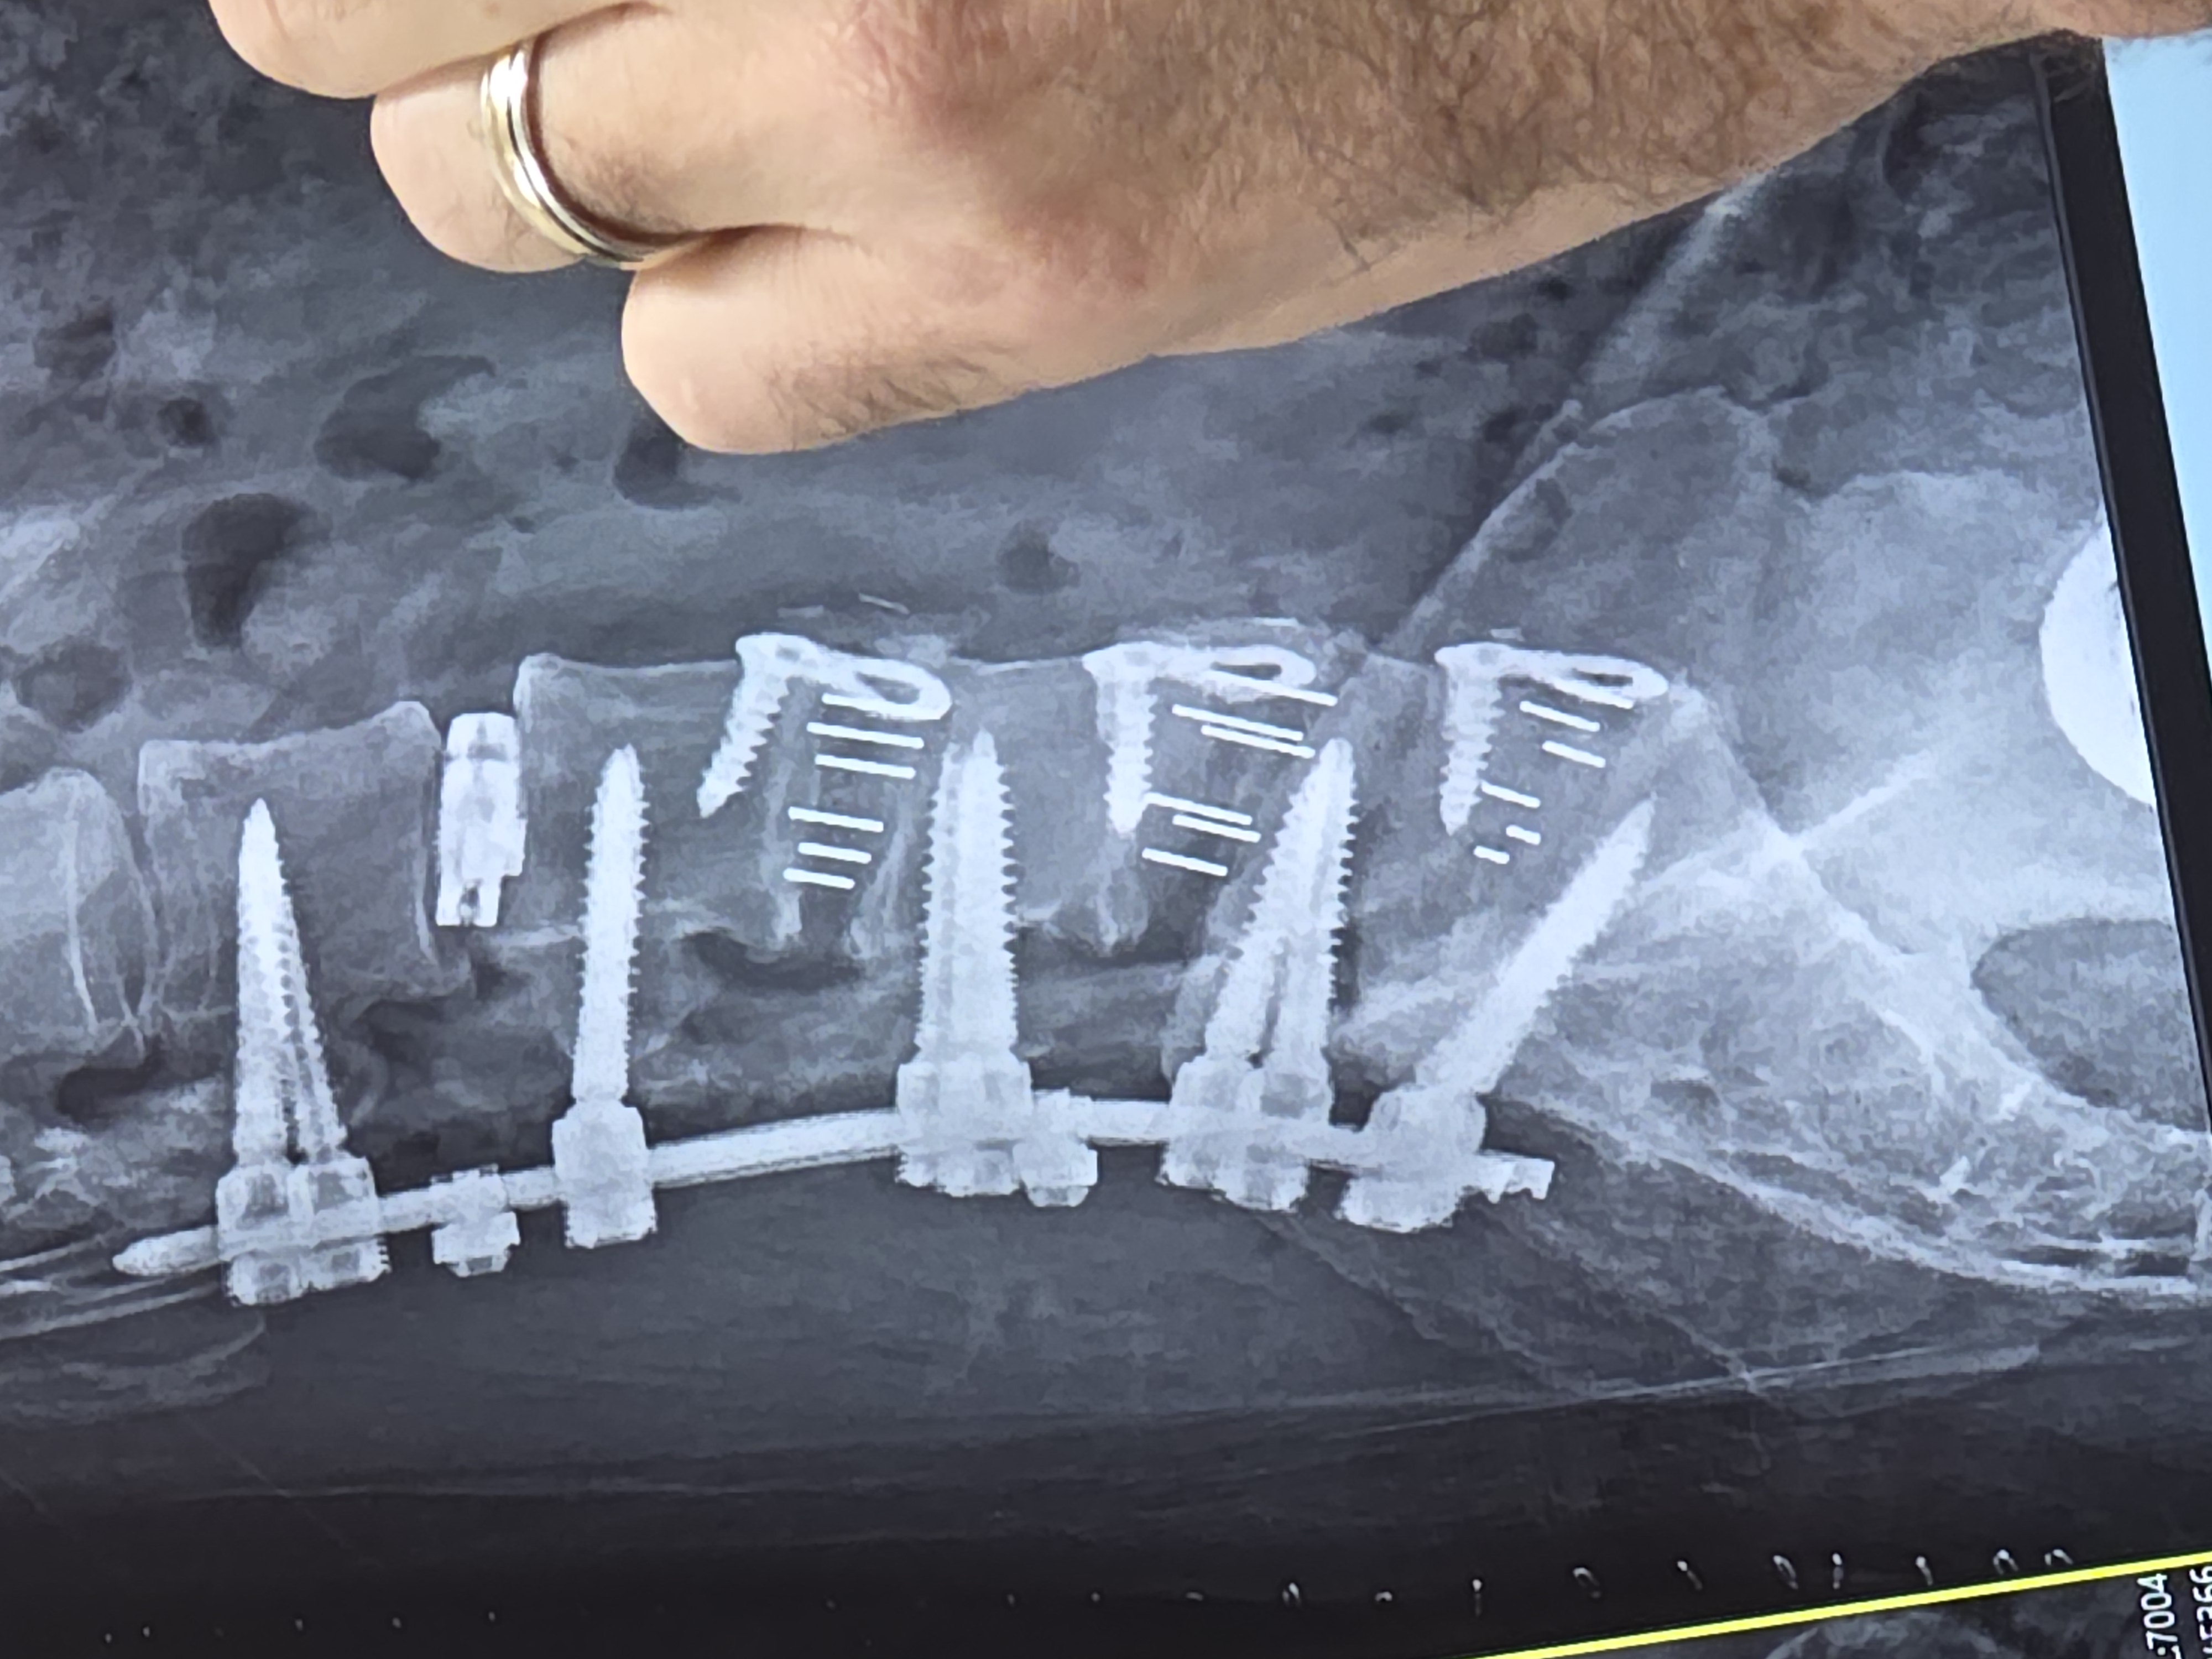

I can probably say more than others and as you read you'll see why.. Met Dr. Courtney in 2021 for bad lumbar accident. First, every time you go, you carry your folder and they give you a gold star...great way to ensure you pay attention. Normally everyone ends with 7, but the record was 17 because it was detailed. I'm over 50 stars. What does that say? Hes bad? No! Says they are very loyal to us. He perforned 360. Lumbar fusion to L3-S1 and he did it but I never got relief. Worsurgeon. wanted another doctorc and delayed and... read more